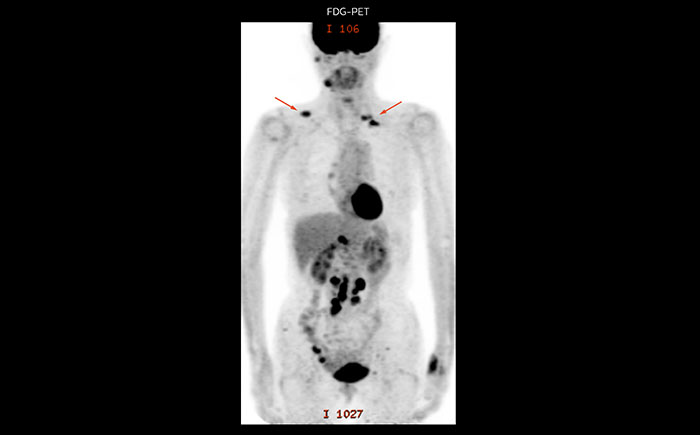

A 61-year-old female with a malignant lymphoma underwent an MRI exam with whole body diffusion weighted imaging (DWIBS) as well as PET. On the images shown, the resolution of DWIBS is better than PET, which allows visualization of the small pelvic lesions and almost no distortion is seen in the neck area.